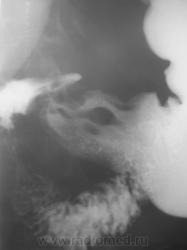

1. Аденоидные полипы в антральном отд. желудка.

Во всяком случае полиповидное выпячивание в антруме налицо, но думаю оно подслизистое... А варикоз - явно не виден, есть в кардии складка небольших размеров, но явно в глаза она не бросается, хотя складки везде толстоваты...

полиповидные образования в антральном отделе +грыжа ПОД

Смею предположить (с учетом наличия + тени кардии желудка по верхне-медиальной стенке, некоторого удлинения и выпрямления кардиального канала, неровности контуров) кардио-эзофагеальный рак без стеноза. В антруме - полипы. Вряд ли подслизистые образования, такие на вершине складок не образуются.

На снимке который поместил Анатолий Владимирович, м.б. или ГПОД (кардиальная) или ахалазия пищевода,при ней газовый пузырь отсутствует или уменьшен в размере. А м.б. и c-r пищеводно-желудочного перехода.

Наблюдение архивное. Я этот снимок привел как типичный пример ампулы пищевода, нормальной, в горизонтальном положении тела, которую наша братия, почти поголовно принимает за грыжу пищеводного отверстия, и соответственно с нашей подачи хирурги пытаются это оперировать...

1.о варикозе вен н\трети пищевода стоит подумать, весьма коварная вещь;

2. полипы препилорического отдела не вызывают сомнения, но что тут интересно - картинка то меняется, периодически крупный дефект выполнения как бы исчезает...но появляется в основании луковицы - сдается мне - это полип на длинной ножке, вот и гуляет он через привратник туда-сюда, вспоминайте - симптом "собачки на цепочке"...

Да, данные ФГДС подтвердили наличие полипов в препилорической части, один действительно - "гулящий" - на длинной ножке.